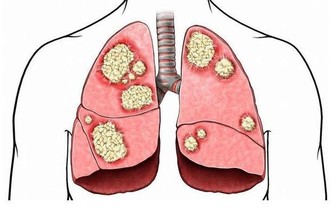

但事實上並非如此,醫生表示說,那是2顆巨大腫瘤,在她的肚子裡面,更可怕的是!

她不僅讓它們在她肚子兩年半,而且也讓她的內臟慢慢被粉碎!

因為那是非常大顆的腫瘤,而且體積大到像是在肚子懷3個小孩一樣!